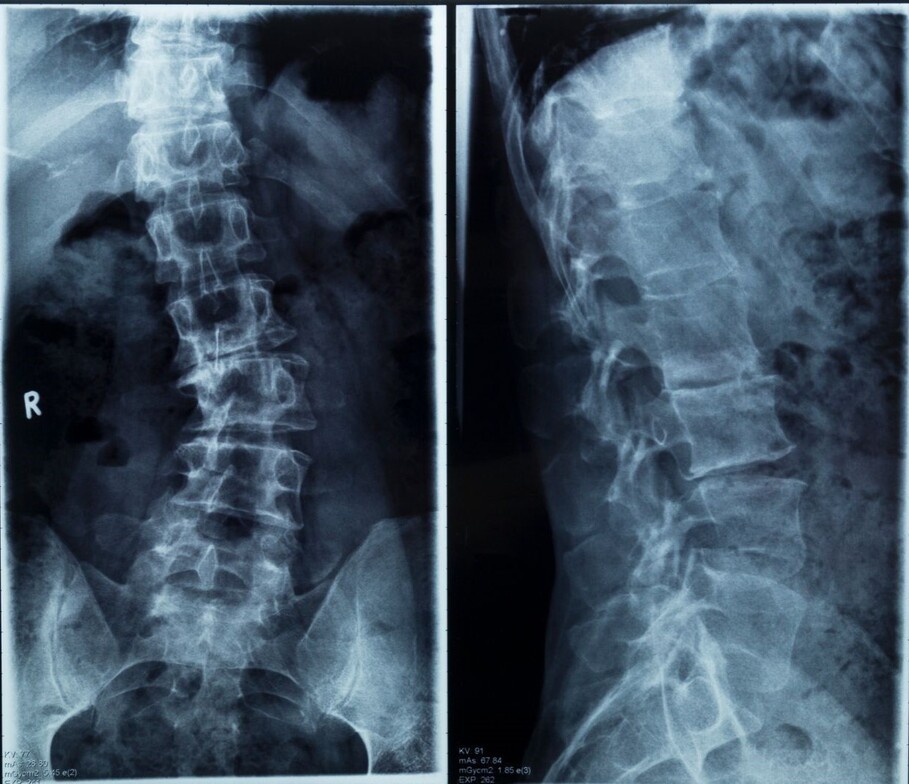

The spine is composed of 24 vertebrae that should curve anterior to posterior (front to back) in the three major regions of the spinal column - Cervical, thoracic, and lumbar. A scoliosis is any lateral curvature of the spine (left to right).

While some curvatures can be minor - resulting in posture changes or tight muscles - others can be severe enough to compress nerves, impair organ function and even prevent you from walking on your own.